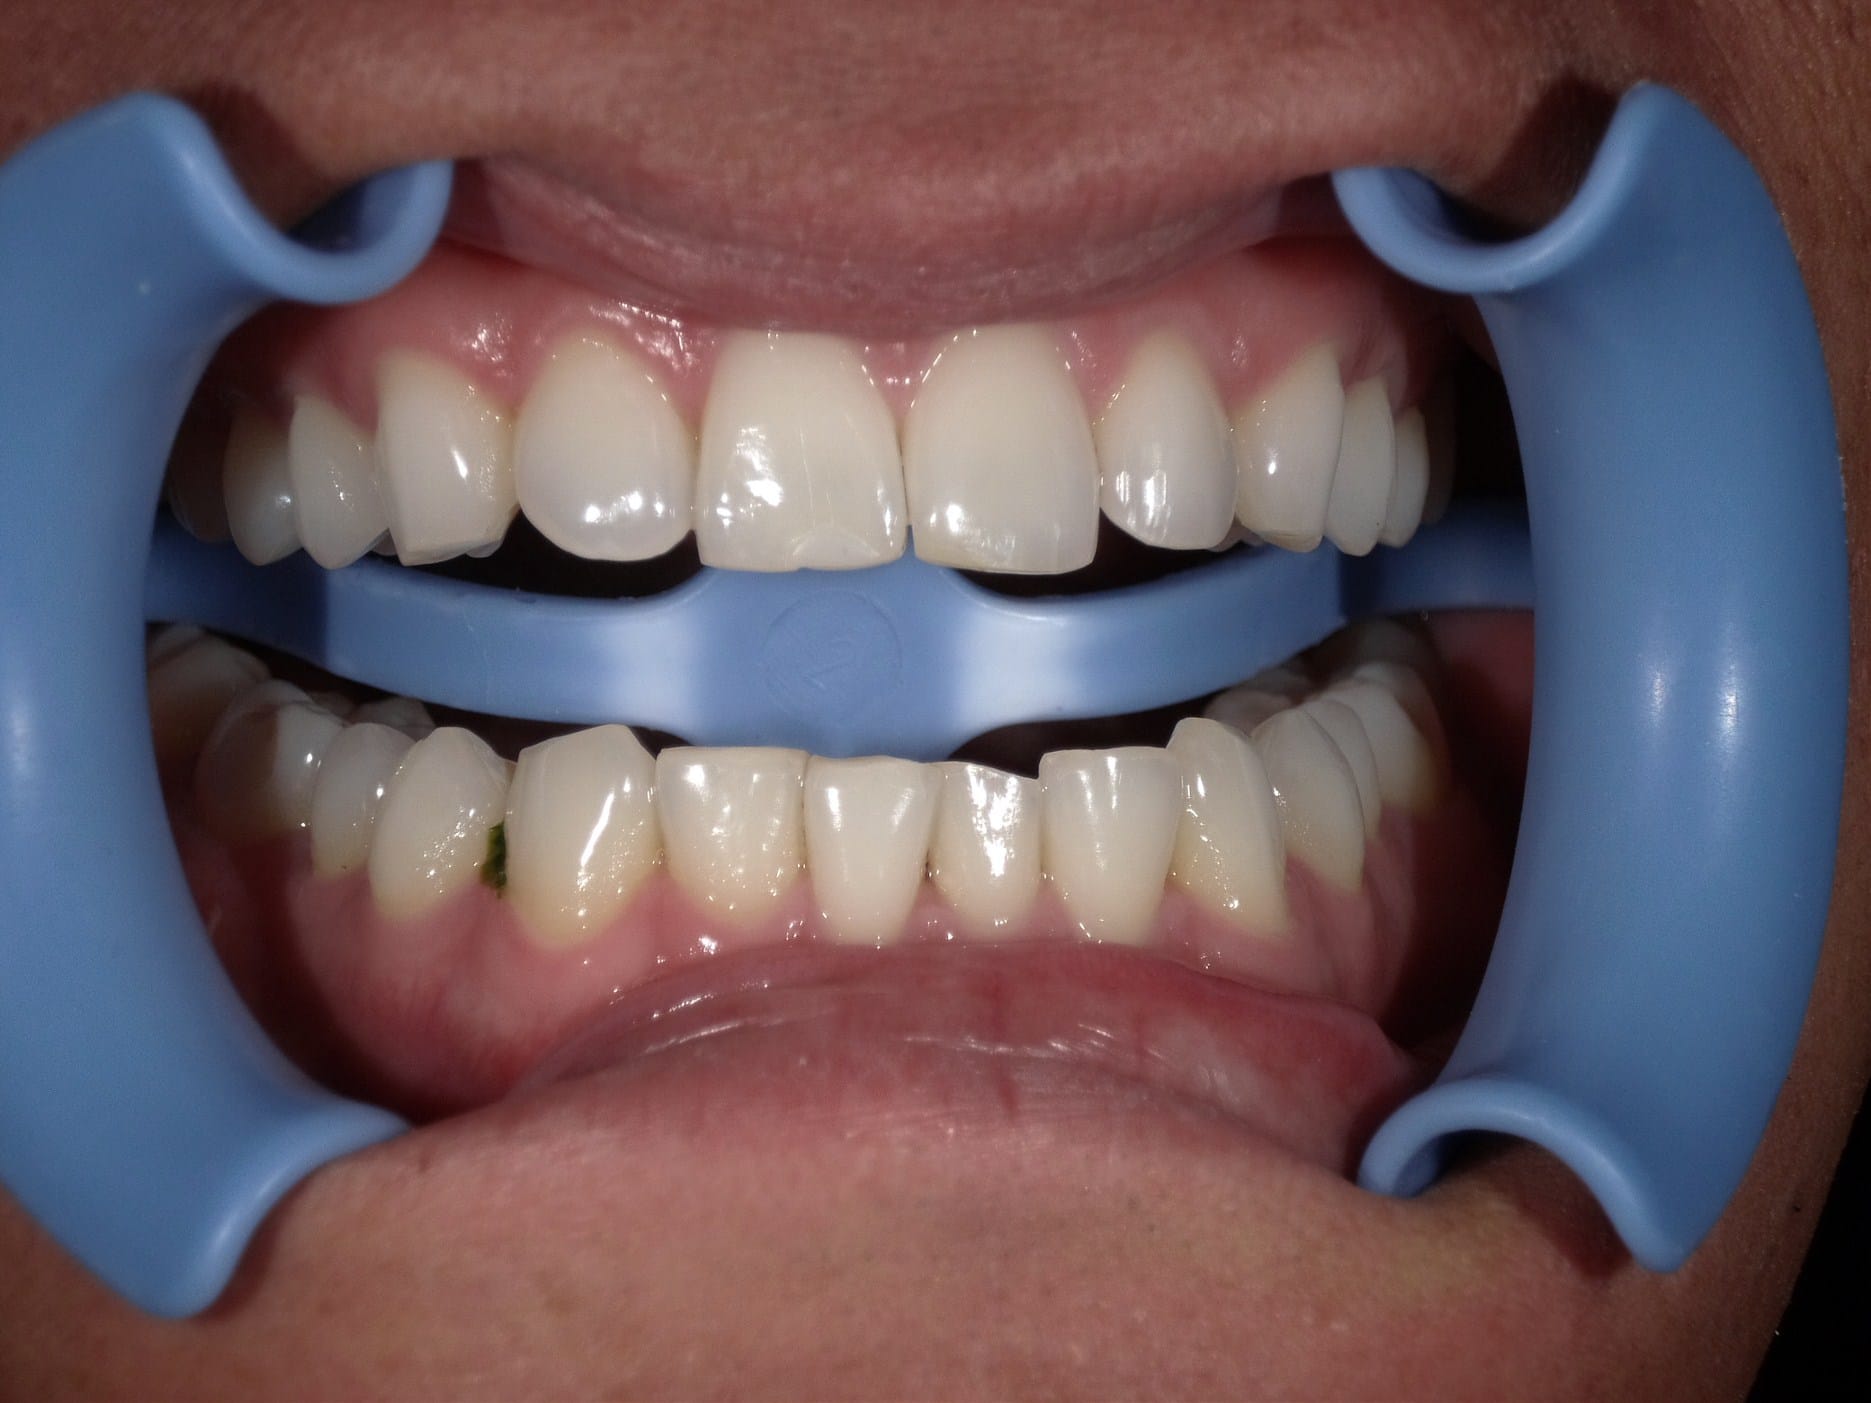

ホワイトニング

Case005 – ホワイトニングト

歯が欠けていて、隙間がある。

歯並びが気になる。

亀裂が入っている。

歯の無いところがある。

見える銀歯が気になる。

綺麗な口元になりたい。

という患者様の診療です。

上はジルコニアセラミックでかけているところを修復しながら、綺麗な歯並びで、患者様のお好きな白い歯に。

下の歯の無い所にはインプラント。

見える銀歯は外して綺麗な歯に修復。

また、ホワイトニングをして上の歯との色のギャップを少なくして、明るい口元にしました。